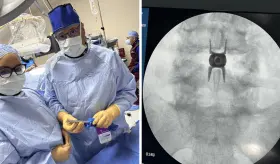

El Centro de Trasplante del Hospital Auxilio Mutuo de Puerto Rico realizó un hito en la medicina, llevó a cabo la primera partición hepática

Puerto Rico transformó su realidad en trasplante hepático en los últimos 14 años, consolidando un programa local que ya suma 516 trasplantes de hígado, cerca de 3.000 renales y 200 pancreáticos, posicionándose entre los líderes de EE.UU.